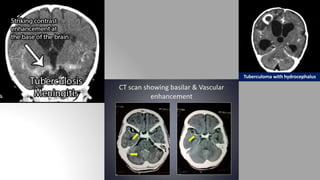

Tubercular meningitis (TBM)

It is to be noted that NCCT may be absolutely normal.

Following are the hallmarks of TBM:

1. Dural thickening and calcification around basal cisterns

2. Enhancing basal exudates involving basal cisterns

3. Cerebral atrophy

4. Infarcts resulting from arteritis

5. Non communicating hydrocephalus

6. Ring enhancing lesions -> Tuberculoma.

Tuberculoma with hydrocephalus